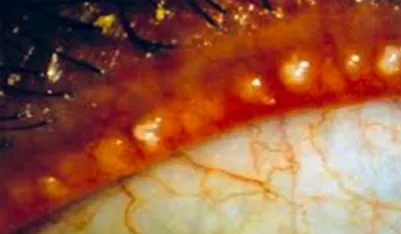

탈락하거나 퇴화한 마이봄(샘)선

염증이 생겨 딱딱하게 굳은 기름샘

정상 마이봄(샘)선

깨끗하고 맑은 기름샘